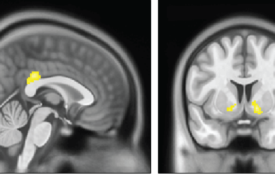

大脑中与奖励和自我控制相关区域的活动可能会提供神经标记,预测人们是否有可能抵抗或屈服于食物等诱惑。

研究人员使用的数据集比之前所有关于该主题的研究的数据集加起来都要大,他们发现大脑大小和认知表现之间存在微小的联系。金宝搏官网登录